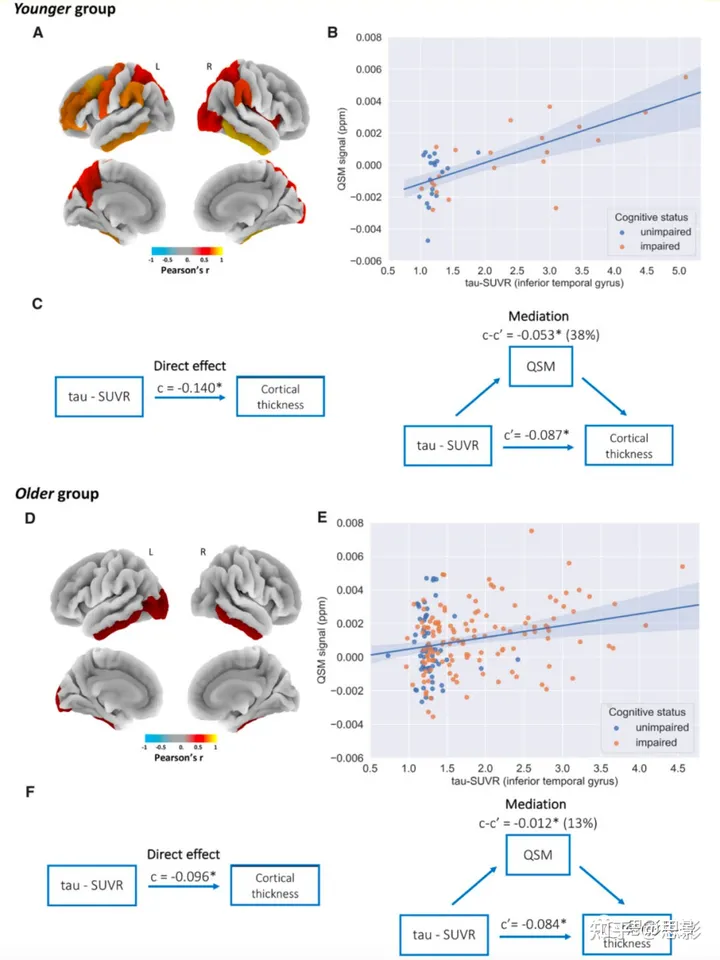

年龄分组显示,QSM与tau-PET之间的关联在年轻的淀粉样蛋白β阳性个体(≤65岁,n=40)中更为明显(图3A、B、D和E,补充表3和4,以及补充图6D和E)(ITG中的回归模型:调整后的R2 = 0.48;tau-PET:β = 0.0015,P < 0.001,CI = 0.001至0.002;Cog组:β = 0.0002,P > 0.7,CI = -0.001至0.001;年龄:β = -0.0002,P = 0.09,CI = 0至2.7×10^-5;性别:β = -0.0005,P > 0.3,CI = -0.001至0.001),而在年长者中则较低(n=196,ITG中的回归模型:调整后的R2 = 0.06;tau-PET:β = 0.0007,P < 0.005,CI = 0至0.001;Cog组:β = 0.0002,P > 0.5,CI = -0.001至0;年龄:β = 3.8×10^-5,P > 0.1,CI = -1.3×10^-5至8.9×10^-5;性别:β = 0.0002,P < 0.2,CI = 0至0.001)。QSM对tau-PET与皮层厚度之间关联的中介效应在年轻组中也更强(中介效应=38%,而对于老年组为13%)(图3C和F),同时还考虑了参与者不同的认知状态(有关按认知状态分层分析结果,请参阅补充资料、补充表3-7和补充图6和9-11)。

图3 年轻组和老年组的区域分析结果。

(A–C) 年轻组的结果(n = 40)。

- 有意义的Pearson相关性在不同脑区之间的区域模式(经过FDR校正,P < 0.05)。颜色标尺代表Pearson相关系数。

- signed-QSM与从颞下沟提取的tau-PET值之间的协变性。回归线周围的半透明区域代表回归估计的95%置信区间。

- 中介分析的流程图(每个模型包括年龄、性别和认知组作为协变量)。c = tau-PET信号与皮层厚度之间的直接关联 [β = -0.14,P < 0.001,CI: -0.20至-0.10];c' = 考虑QSM效应的tau-PET信号与皮层厚度之间的关联 [β = -0.087,P < 0.005,CI: -0.145至-0.03];c-c' = QSM的中介效应 [β = -0.053,P < 0.005,CI: -0.104至-0.02,QSM解释了tau-PET信号对皮层厚度的38%(β比率)的影响]。

(D–F) 老年组的结果(n = 196)。 - 在多重比较下,经过FDR校正的signed-QSM与tau-PET信号之间的Pearson积矩相关性生存的脑区(P < 0.05)。颜色标尺代表Pearson相关系数。

- 颞下沟的signed-QSM与tau-PET信号之间的相关性。回归线周围的半透明区域代表回归估计的95%置信区间。

- 中介分析的图表(每个模型包括年龄、性别和认知组作为协变量)。c = tau-PET信号与皮层厚度之间的直接关联 [β = -0.096,P < 0.001,CI: -0.128至-0.07];c' = 考虑QSM效应的tau-PET信号与皮层厚度之间的关联 [β = -0.084,P < 0.001,CI: -0.116至-0.05];c-c' = QSM的中介效应 [β = -0.012,P < 0.01,CI: -0.023至0,QSM介导了tau-PET信号对皮层厚度的13%(β比率)的影响]。